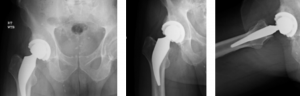

A 67-year-old Caucasian female weighing 190lbs diagnosed with osteo/degenerative arthritis received Advita’s Alteon® Neck Preserving Stem with a Biolox®delta femoral head and Novation® Crown Cup acetabular shell. The patient went under general anesthesia using a direct anterior surgical approach with an incision size of 10cm. There was an estimated blood loss of 150cc and surgery duration was 41 minutes. The patient was discharged after one day postoperative with a walker to in-home care for rehabilitation.

Pre-Op AP Pelvis

Harris Hip Score 37 (max=100) | Oxford Hip Score 19 (max=48)

6-Week Post-Op

Harris Hip Score 98 (max=100) | Oxford Hip Score N/A

3-Month Post-Op

Harris Hip Score 94 (max=100) | Oxford Hip Score 43 (max=48)

1-Year Post-Op

Harris Hip Score 100 (max=100) | Oxford Hip Score 48 (max=48)

CONCLUSION

Before surgery, this patient presented low Harris Hip and Oxford Hip scores. Once she reached her one-year follow up, her scores increased by more than 63.0 percent on the Harris Hip and 60.4 percent on the Oxford Hip. The patient is satisfied with her total hip replacement with the direct anterior approach, which has been associated with faster functional recovery than the posterolateral approach. The outcomes of her surgery continue to be followed annually. •